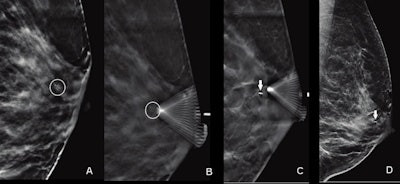

Digital breast tomosynthesis (DBT)-guided biopsy can help reduce patient discomfort and radiation exposure when it comes to suspicious breast calcifications, a study published September 14 in the American Journal of Roentgenology found.

Researchers led by Dr. Derek Nguyen from Johns Hopkins Medicine compared DBT-guided biopsy with conventional stereotactic-guided digital mammography biopsy and found that clinical outcomes were not affected, making DBT a potential alternative.

DBT continues to grow in use in breast care practices across the world as new research highlights its advantages over digital mammography. Previous research has shown that DBT-guided biopsy improves targeting and sampling of noncalcified lesions such as asymmetries, masses, and architectural distortion.

Suspicious calcifications are "the most common" imaging finding tied to ductal carcinoma in situ (DCIS) and have a broad positive predictive value for malignancy, researchers noted. Digital mammography is typically used to guide biopsy for these calcifications, which uses multiple exposures to better target the area of interest in 3D.